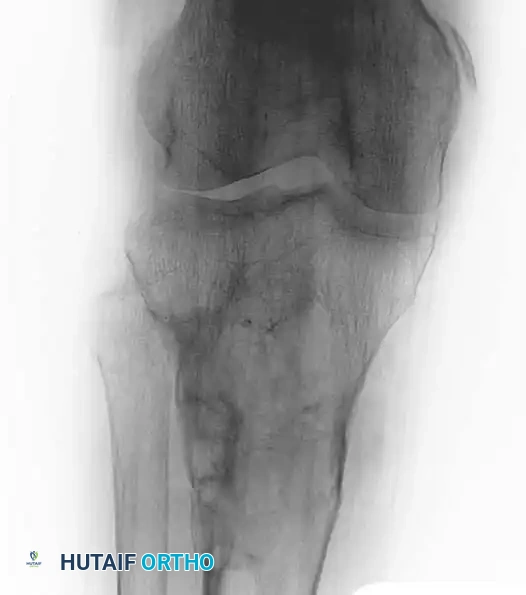

Fig. 20-22: (A and B) Pathological fracture of the right proximal tibia occurring through a large, expansile “brown tumor” of hyperparathyroidism in a 55-year-old woman.

Primary treatment is medical or surgical management of the underlying endocrinopathy (e.g., parathyroidectomy) by an endocrinologist or general surgeon. Following normalization of PTH levels, brown tumors typically remineralize and regress spontaneously. Orthopedic intervention is strictly limited to the stabilization of actual or impending pathological fractures. If a fracture occurs, intramedullary nailing or rigid plate osteosynthesis is required, as the structural integrity of the bone is severely compromised.